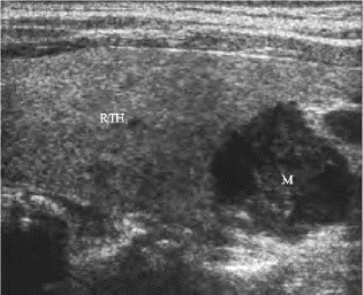

图7-10 甲状旁腺腺癌声像图

甲状腺右叶下极后缘可见一个较大的低回声结节,形态不甚规整,颈部淋巴结转移,远端骨转移

甲状旁腺癌病人临床较少见,只有约1%的原发性甲状旁腺功能亢进由甲状旁腺腺癌引起。甲状旁腺腺癌生长缓慢,一般仅在颈部局限性扩散,只有极少数发生远处的骨及肺部转移。

超声表现:瘤体较腺瘤大,呈实性低回声,形态不甚规整,可向周围组织浸润,具有典型的甲状旁腺功能亢进症状,复发者内部可见细密点状钙化。CDFI显示内部动脉血供较为丰富,血流走行扭曲,流速增快。